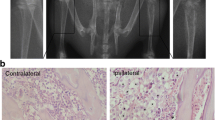

To elucidate the mechanism underlying bone cancer pain, we analyzed the activity of glia and expressions of IL-6, IL-18, IL-1β, and TNF-α in the spinal cord. The activation of microglia was first evident on day 4 and reached a peak on day 7 after intra-tibia inoculation of Walker 256 mammary gland carcinoma cells (Fig. 2). On day 10, the activity of microglia decreased under the level on day 4. The activation of astrocytes was first evident on day 10 (Fig. 3). This suggested an acute role of microglial in bone cancer pain. And astrocytes contributed to the maintenance of bone cancer pain. In addition, increases in IL-6, IL-18, IL-1β, and TNF-α levels were first evident at day 4 after tibia inoculation with cancer cells and continued to day 10 (Fig. 4). In contrast, there were no differences observed in the sham group during the various time points.

The activity of spinal astrocytes in tumor-bearing rats (n = 5 for each group). Immunostaining of the green reaction product for spinal GFAP before surgery (a), 4 days (b), 7 days (c), and 10 days (d) after surgery were shown in the left panel. The immunofluorescence densities of GFAP in different groups were shown in the right panel. Scale bar = 100 μm. Magnification ×200. Spinal astrocytes were only significantly activated on day 10 after intra-tibia inoculation of Walker 256 mammary gland carcinoma cells. These were no difference on day 4 and day 7. *P < 0.05 vs. baseline.

Astrocytes are the most abundant cells in the CNS, and previous studies have demonstrated that astrocytes play a key role in the maintenance of neuropathic pain [37]. In our experiment, we also found astrocytic activation followed the microglial response, and astrocytes might maintain the state of bone cancer pain. Then, we went on to investigate the stimulatory effect of JWH-015 on the activities of astrocytes using immunostaining (Fig. 6). At 10 days after tibia inoculation with Walker 256 rat mammary gland carcinoma cells, a significant increase in the staining density of GFAP was observed in the dorsal horn (P < 0.05). This increase was inhibited by JWH-015. However, this change was only statistically significant at 24 h after JWH-015 treatment and could be completely prevented by pretreatment with AM630. As time passed, the staining density returned to normal levels (approximately equal to the level before JWH-015 treatment). No corresponding changes were observed in the vehicle-treated group.

JWH-015 inhibited the activation of astrocytes induced by bone cancer pain. Immunostaining of the green reaction product for GFAP in the ipsilateral dorsal horn before surgery (a), 10 days after surgery (b), 6 h (c), 24 h (d), and 72 h (e) at different groups. Scale bar = 100 μm. Magnification ×200. On day 10, the astrocytes were activated in the tumor-bearing rats, but this activation was inhibited by JWH-015. JWH-015 displayed a time-dependent effect on astrocytes, which was only significant 24 h after JWH-015 treatment and could be prevented by pretreatment with AM630. No corresponding changes were observed in the DMSO-treated group rats. *P < 0.05 vs. day 10, **P < 0.01 vs. day 10.